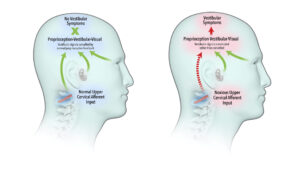

良性発作性頭位めまい症(BPPV)または原因不明のめまい後に残存症状を経験する患者は約60-80%に達します。時間が解決してくれるだろうと漠然と期待しますが、実際には数ヶ月〜数年、さらには十数年以上続くのを目にします。

3年前のBPPV後、意識が朦朧としてふらつきます

BPPV後に解決されない様々な症状を訴えて、ある患者さんが来院されました。

2年間の胃のむかつき、繰り返すめまい、耳閉感、聴覚過敏に不安感まで